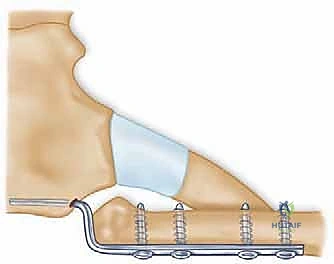

Modern stabilization relies on robust biological reconstruction. While primary repair of the capsule using suture anchors in the manubrium can augment the construct, a figure-of-eight graft reconstruction is the gold standard for restoring multiplanar stability. A semitendinosus or gracilis autograft (or allograft to minimize donor site morbidity) is preferred due to its length and tensile strength.

Drill holes, typically 4.0mm to 4.5mm in diameter, are meticulously created. In the medial clavicle, two holes are drilled from anterior to posterior, approximately 1 cm lateral to the articular margin and 1 cm apart. In the manubrium, two corresponding holes are drilled. Critical Step: When drilling the manubrium and the clavicle, a malleable retractor or a broad periosteal elevator must be placed deep to the bone to protect the mediastinal structures from the drill bit plunging. The drill must always be directed from anterior to posterior, with precise control.

The graft is then passed in a figure-of-eight configuration. Suture passing wires or curved shuttles are used to navigate the graft through the osseous tunnels. The graft is tensioned with the clavicle held in anatomical reduction (often requiring downward and posterior pressure on the medial clavicle). The graft limbs are then sutured to themselves and to the surrounding periosteal tissues using heavy, non-absorbable, braided sutures.

Some modern techniques utilize a "docking" method, where the graft is fixed into blind-ended sockets using biocomposite tenodesis screws, minimizing the need for posterior dissection and reducing the risk to mediastinal structures. Regardless of the specific graft routing, the final construct must be rigidly stable through a functional range of motion on the operating table.